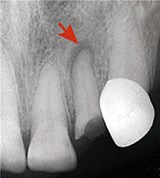

Заболевание требует неотложного вмешательства стоматолога: обеспечивают отток экссудата от верхушки корня зуба, прочищают его корневой канал. При выраженных воспалительных явлениях назначают антибиотики, электрофорез, УВЧ-терапию и др. Лечение завершают пломбированием корневых каналов. В сильно запущенных случаях зуб приходится удалять.